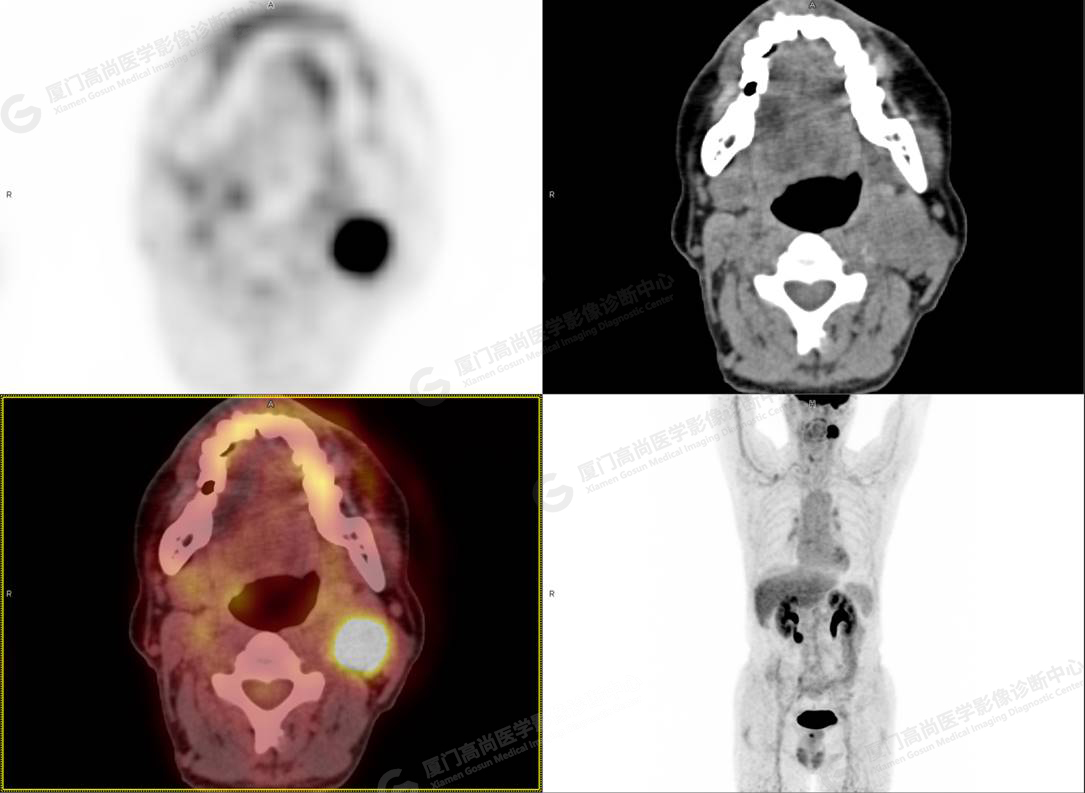

圖2

PET/CT所見:左側(cè)頸部(II區(qū))見腫大淋巴結(jié),大小約2.5cm×2.3cm,其內(nèi)密度不均,邊界尚清,放射性攝取異常增高,早期SUVmax 11.5,延時SUVmax 14.5。

影像診斷: 左側(cè)頸部(II區(qū))腫大淋巴結(jié),代謝異常增高,考慮腫瘤性病變可能性大(淋巴瘤?轉(zhuǎn)移瘤?),建議病理學(xué)檢查明確。